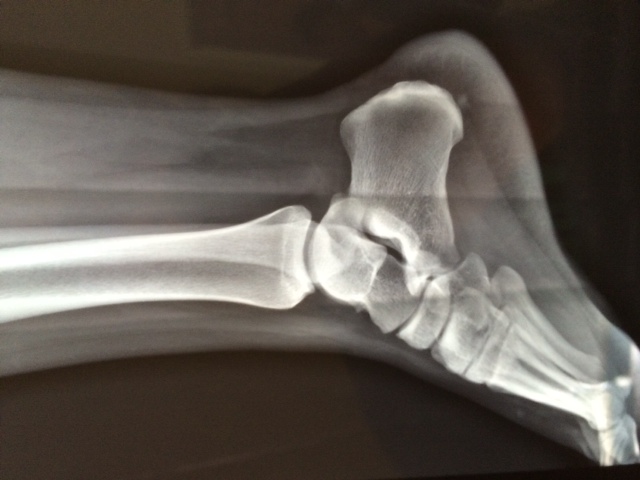

The assessment and management of lateral ankle ligament injuries

The assessment and management, as well as the clinical examination, special investigations and treatment of sports-related lateral ankle ligament injuries, are summarised for the general practitioner. Practical advice is discussed, when identifying and diagnosing chronic ankle injuries, and subsequent referral for specialist involvement.